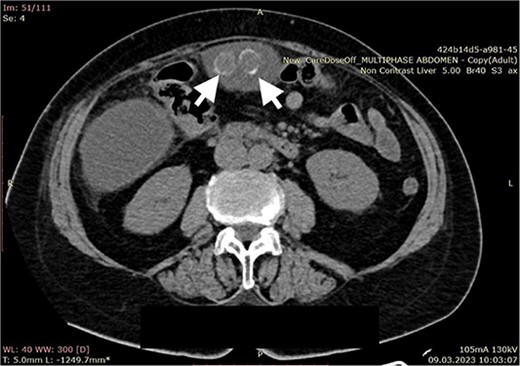

A 70-year-old female patient was transferred to our emergency department from another hospital with abdominal pain and vomiting in the past 2 weeks. The patient presented with clinical signs of acute abdomen. Physical examination showed diffuse abdominal tenderness. Abnormal laboratory findings comprehended Leucocyte count of 12.01 (3.5–10.0 × 109 g/L), Thrombocyte count of 456 (150.0–300.0 × 109 g/L), Neutrophil count of 9.7 (1.2–8.0 × 109 g/L), serum direct bilirubin value of 11.10 (0.0–8.6 mmol/L), and C-reactive protein value of 258 (0.0–5.0 mg/L). An abdominal computerized tomography (CT) scan revealed a large collection of fluid in the right hemiabdomen (Figs 1 and 2) and free gallstones in the abdominal cavity (Fig. 3).

Computerized abdominal tomography (axial scan) showing two free gallstones in the intraabdominal cavity (arrows).